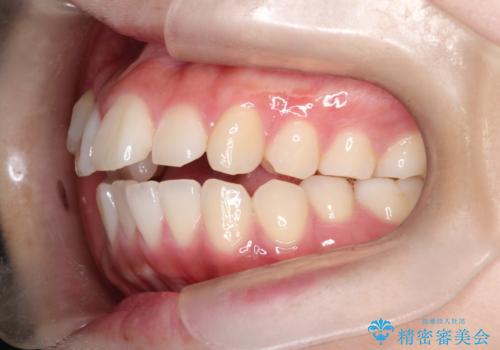

【ワイヤー矯正】オープンバイトを治したい

主訴のオープンバイトは改善し、抜歯をしたことで前歯が下がり綺麗になりました。抜歯矯正でしたが1年2か月という短い期間で終了しました。